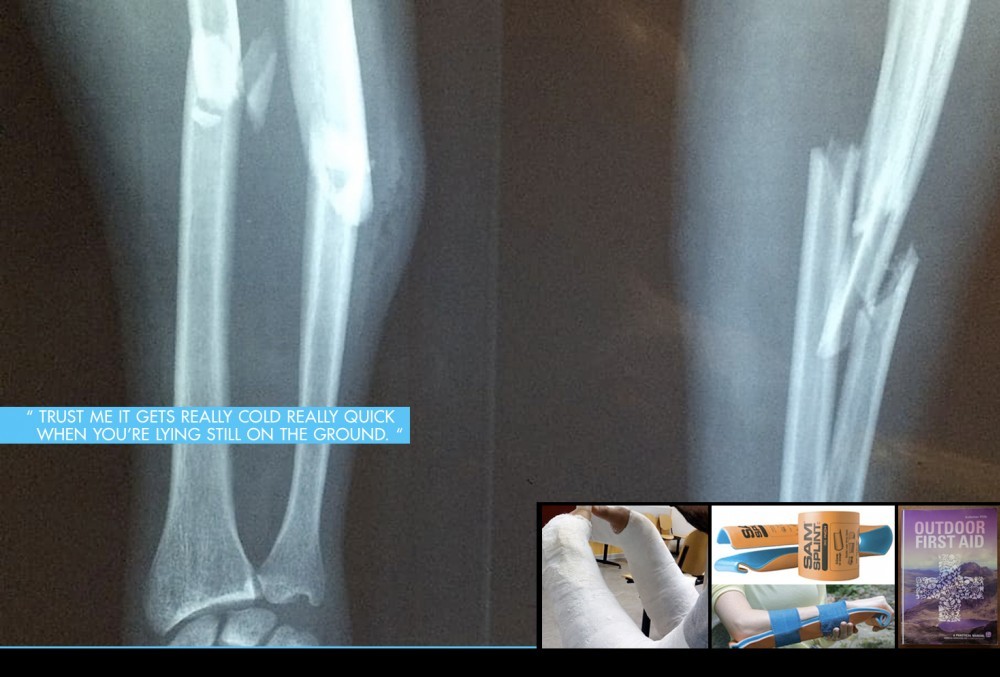

In case of a fracture or dislocation, things are a bit more tricky. When seeing your buddies arm or leg flexing in ways only cartoons characters do, it's safe to assume your riding day is done. In this case, you’re better off focussing on stabilizing, and setting up a rescue operation by mountain rescue. Make sure the unlucky one is comfortable and especially stays warm.

In some situations staying where you are isn’t an option. If you’ve paid attention when at the first aid course you can consider making a splint to stabilize the floppy limb to prevent further damage. You can get creative with sticks and branches, but the SAM Splint and some medical tape will do a better job. It is made of a bendable aluminium core, covered in foam. Reusable and easy to pack it can be a great addition to your kit, especially if you ride in remote areas or in places where you don’t easily find sticks.